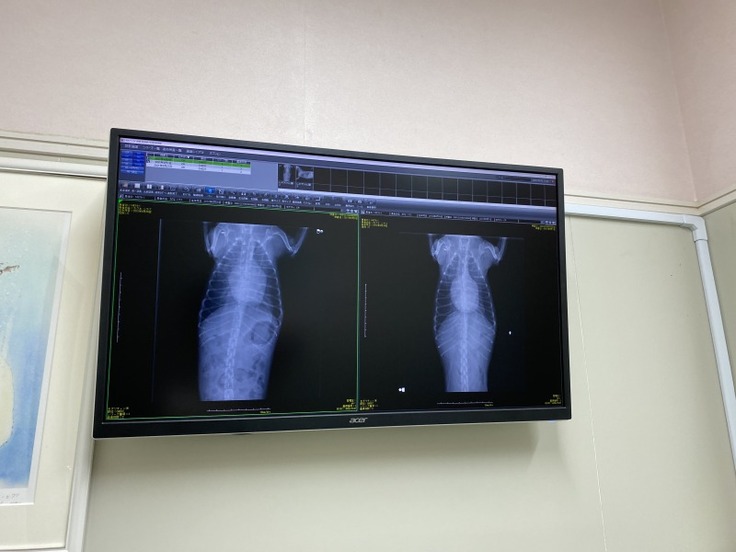

(しらすの肥大した心臓)

(右9/1撮影、左9/9撮影)